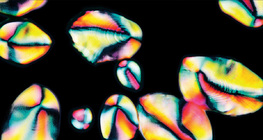

zumiranje: 200x